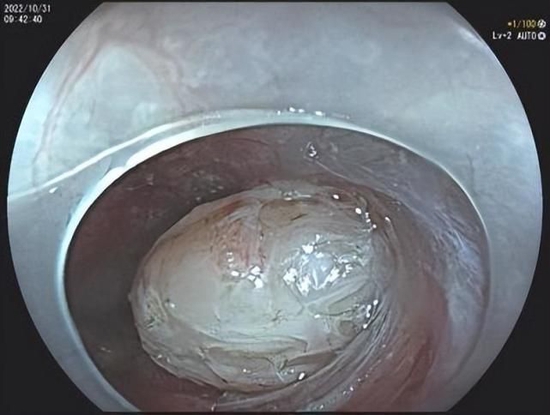

发现并剥离病变

经过术前充分的准备,消化内科陈镇医生为患者实施经内镜粘膜下隧道肿瘤切除术(STER),历时1个小时,直径约3cm的病变顺利切除。术后王大娘无任何不适,经适当禁食及药物治疗后已恢复饮食,术后病理证实为食管平滑肌瘤。

STER手术在食管、胃食管结合部、胃窦等部位,先在黏膜表面开一个小口,随后将内镜深入其中,在黏膜下层建立一个隧道探查并分离病变,在直视下将肿瘤完整切除,同时保留了消化道表面黏膜的完整性,在肿瘤完整切除后,将黏膜隧道的开口使用金属夹进行夹闭,避免了消化道的穿孔,减少了感染等并发症。